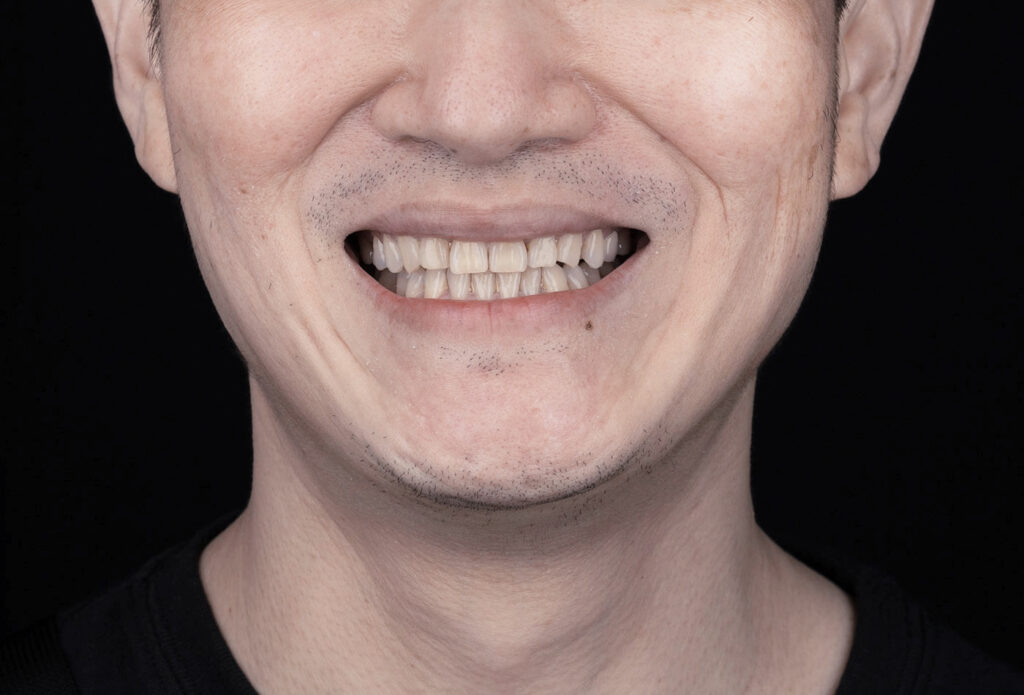

門牙開縫想改善

L先生 隱形牙套矯正+顯微補牙

- 術後 - 隱形矯正解決排列問題